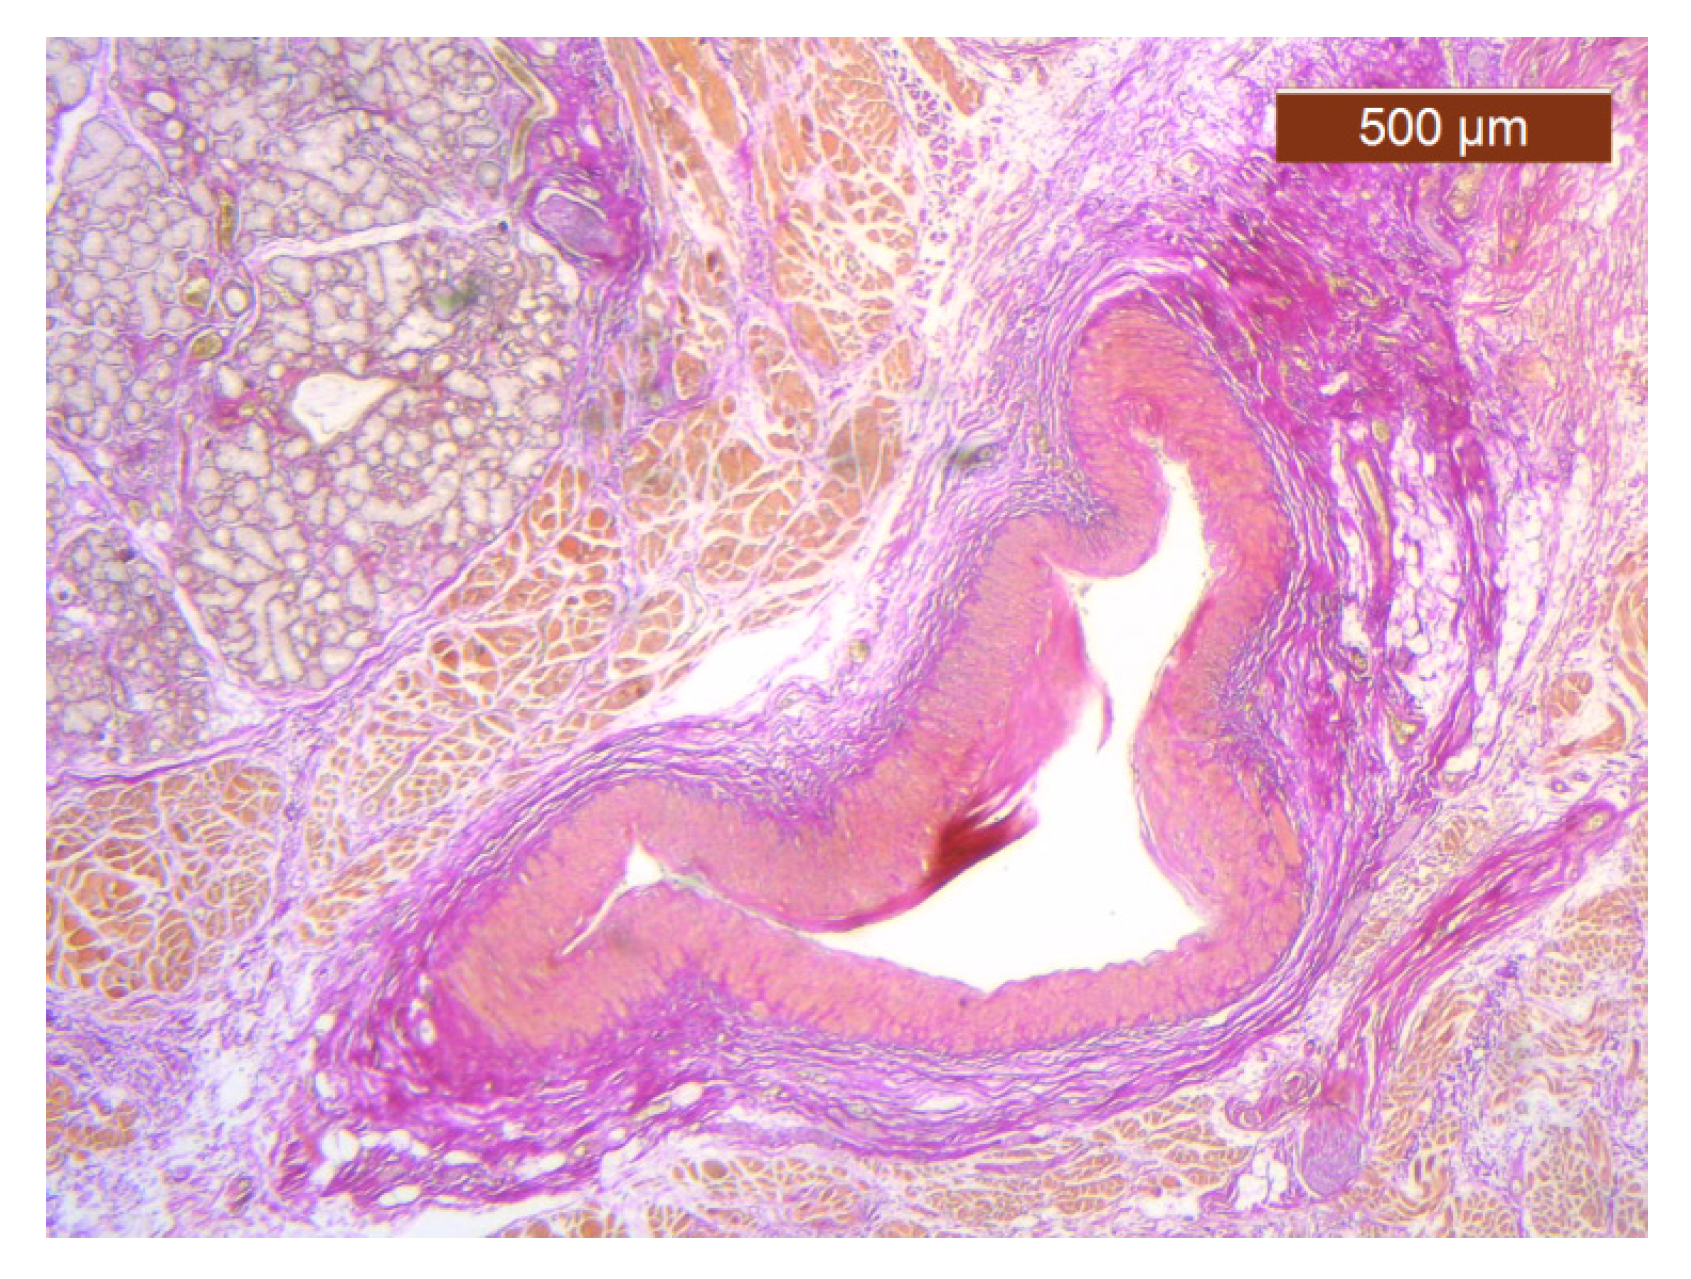

The region of the nose located medial to the nasolabial fold also presented distinct characteristics at the level of the SMAS bed. The collagen fibers had the densest appearance among the explored regions (Figure 18). This three-dimensional collagen network is distributed toward the superficial dermis and also descends into the deep dermis. At this level, it delimits and seals the large blood vessels (Figure 18, Figure 19 and Figure 20).

Figure 18. Collagen fiber meshwork and a large blood vessel with thick walls and lobules of adipose tissue (HE ×2.5).

Figure 19. Details of collagen fiber meshwork and a large blood vessel with thick walls and lobules of adipose tissue (HE ×2.5).